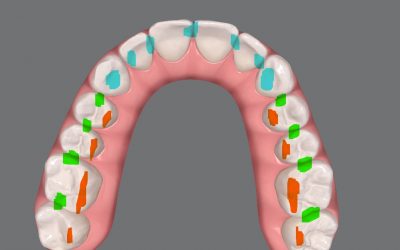

Trabajamos tus casos buscando la más alta predictibilidad de movimientos.

ClinCheck

iOrtho

Approver

QuickCheck